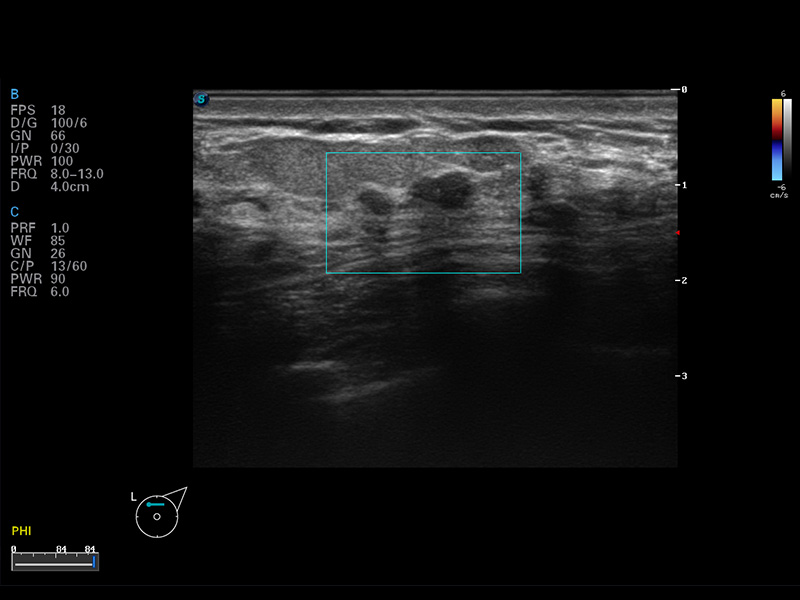

实时宽景成像

空间复合成像